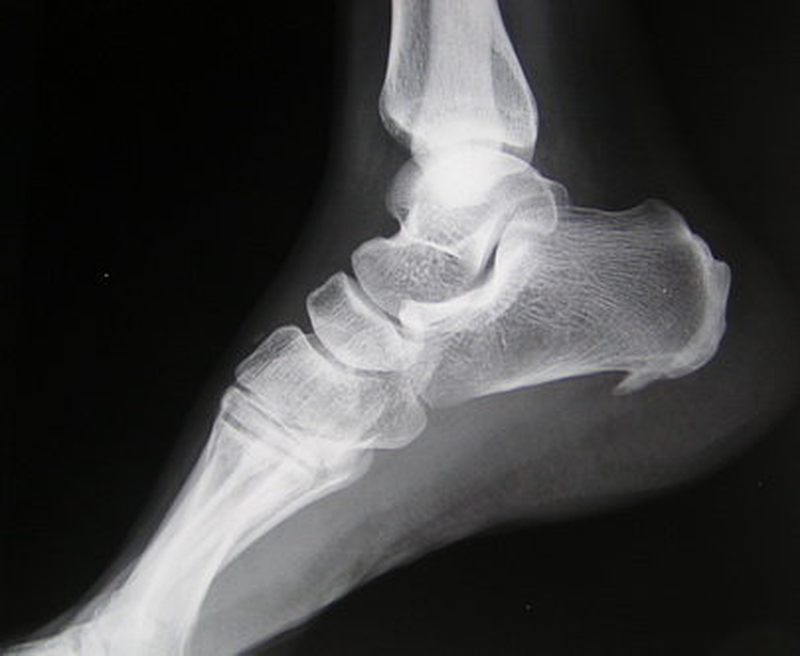

Viêm cân gan chân bao lâu thì khỏi ? Bệnh viện nào tại TPHCM có thể điều trị viêm cân gan chân lâu năm 2 Hình chụp phần xương của một bệnh nhân mắc viêm cân gan chân.

Đây là một cơ chế bệnh lý chung viêm cân gan mãn tính mà nguyên nhân là do nhiều lần bị chấn thương nhỏ, lặp lại nhiều lần kèm theo tình trạng thiếu máu nuôi gân. Có thể hiểu cọng gân chân như một dây thép, bẻ một lần dây thép không đứt nhưng nếu cứ bẻ qua lại nhiều lần thì sẽ bị đứt.

Các yếu tố để đánh giá chính xác tình trạng của bạn bao gồm: Độ săn cơ bắp, sự thăng bằng, phản xạ, cảm giác khi nhìn và chạm, sự phối hợp. Bạn cũng có thể chụp X-ray hoặc MRI để xác định được chỗ gãy trong xương.